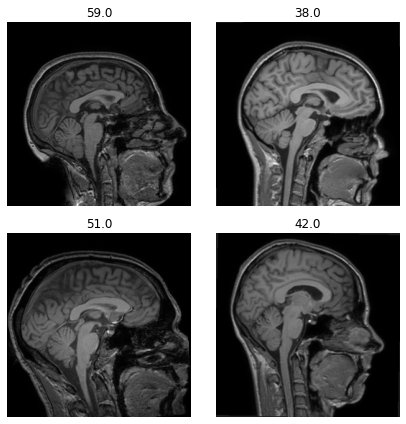

dls.show_batch(anatomical_plane=2)